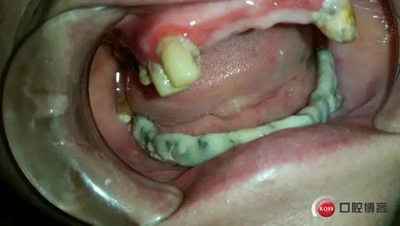

戴牙

開嘴效果

全過程約70日。因下牙槽骨較低,事前拍全景片。至今完成修復3個月,咀嚼效果良好。